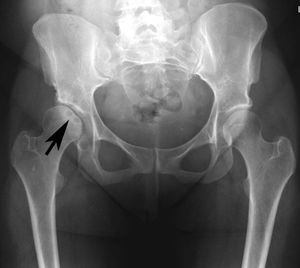

Avascular Necrosis of the femoral head

AVN of the femoral head is a common complication in patients with sickle cell disease (SCD), and collapse of the femoral head occurs in 90% of the patients within five years of the diagnosis of osteonecrosis.